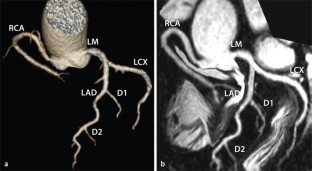

Bei symptomatischen Patienten wird die Indikation zur Koronarangiographie mittels Computertomographie (CT) dann gesehen, wenn eine stenosierende koronare Herzkrankheit (KHK) als Ursache der Beschwerden ausgeschlossen werden soll und der Patient eine mittlere Vortestwahrscheinlichkeit für eine KHK hat. Angemessen erscheint der Einsatz der CT-Koronarangiographie auch dann, wenn ein Belastungstest nicht eindeutig ausfiel, sodass der weitere therapeutische Weg nicht klar ist. Mitunter kann bei einem Patienten, der trotz hoher Wahrscheinlichkeit einer invasiv behandlungsbedürftigen KHK die eigentlich notwendige invasive Koronarangiographie ablehnt, durch das Ergebnis einer CT-Koronarangiographie die Bereitschaft zur invasiven Diagnostik gebahnt werden.

Coronary angiography by computed tomography (CTCA) is most suitable for symptomatic patients with an intermediate likelihood to exclude a coronary stenosis as the cause of the symptoms. It would also be appropriate in a patient in whom an equivoval stress test result has led to uncertainty about the patient’s further management. CTCA may occasionally be acceptable in a high risk symptomatic patient who refuses the necessary invasive coronary angiography if the results of CTCA are likely to alter patient management.